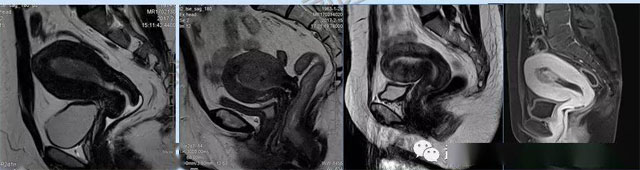

婦科疾病常常讓女性陷入了焦慮。主要是這類(lèi)疾病婦女有難言之隱,癥狀隱匿,病情復(fù)雜。磁共振體檢車(chē)的金光火眼能力可以破解各種婦科難題。哪些情況需要使用磁共振檢查,檢查過(guò)程是否有不適。這些都是可以解決的。例如子宮常見(jiàn)疾病的磁共振診斷。

磁共振VS傳統(tǒng)檢查:有這些優(yōu)勢(shì)?無(wú)輻射安全系數(shù)高,磁共振沒(méi)有電離輻射,適合備孕跟孕婦檢查。它對(duì)軟組織有高清的成像效果,可以清晰的看到子宮各層的結(jié)構(gòu)。可以識(shí)別細(xì)小的肌瘤,早期的癌癥腫瘤??梢园l(fā)現(xiàn)其他設(shè)備難以檢查到的深部子宮內(nèi)膜異位結(jié)節(jié)。多序列成像和增強(qiáng)掃描檢查,判斷腫瘤的良性準(zhǔn)確率高達(dá)90%以上。